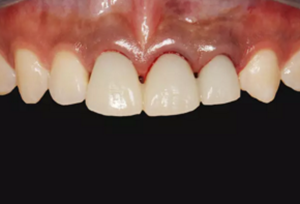

(4)最終修復(fù)。種植體周圍軟組織改建成熟以后,進行最終修復(fù)。本 病例采用兩步法印模技術(shù)精確記錄種植體的三維位置和種植體周圍軟組織穿 齦輪廓外形。 首先,口內(nèi)制取臨時冠及周圍軟硬組織的硅橡膠陰模,復(fù)制軟硬組織 表面形態(tài)。然后,取下臨時修復(fù)體,常規(guī)制取閉窗式種植體水平聚醚印模, 精確記錄種植體的三維位置,灌制含人工牙齦的超硬石膏模型。最后,去除 模型上的人工牙齦,將臨時修復(fù)體戴入到模型上,在臨時修復(fù)體周圍和硅橡 膠陰模內(nèi)注入人工牙齦,將陰模就位到含臨時冠的石膏模型上,精確轉(zhuǎn)移穿齦輪廓外形,獲得工作模型。 制作螺絲固位的一體化氧化鋯基臺冠,以切削方式制作完成后,表面 添加飾瓷來獲得理想的美觀效果。 術(shù)后7個月,戴入最終修復(fù)體,紅白美學(xué)效果滿意。

(5)復(fù)查。種植體周圍骨水平穩(wěn)定,齦乳頭及齦高點位置穩(wěn)定,齦緣 曲線形態(tài)理想,唇側(cè)軟硬輪廓良好,功能滿意,修復(fù)效果符合預(yù)期。

圖23 最終修復(fù)后即刻口內(nèi)像

圖25 最終修復(fù)后復(fù)查口內(nèi)像

本病例在觀察期內(nèi),種植修復(fù)獲得了良好的軟硬組織美學(xué)效果和穩(wěn)定 性?;颊邔χ委熜Ч麧M意。